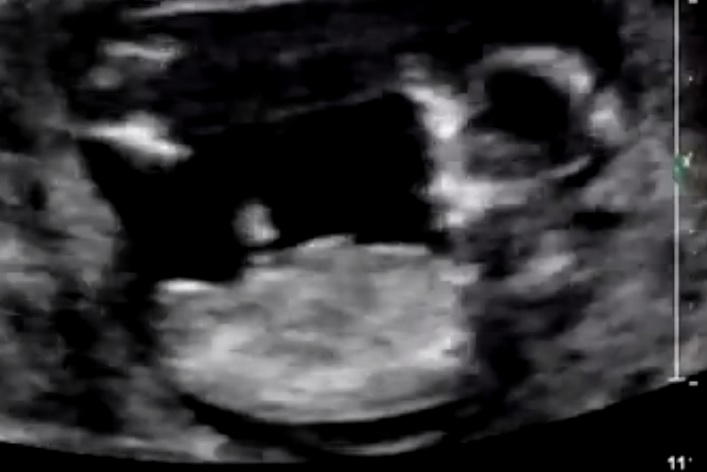

Hi, this is my scan at 13 weeks 4 days would love to hear people's opinions on gender. Thanks very much :)